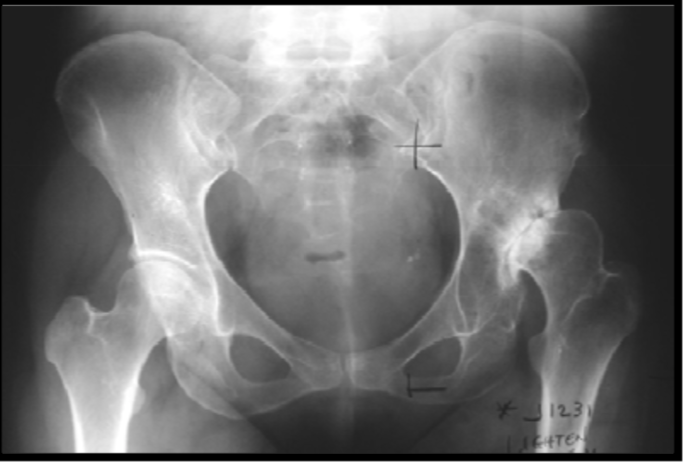

Developmental dysplasia of the hip

déformation